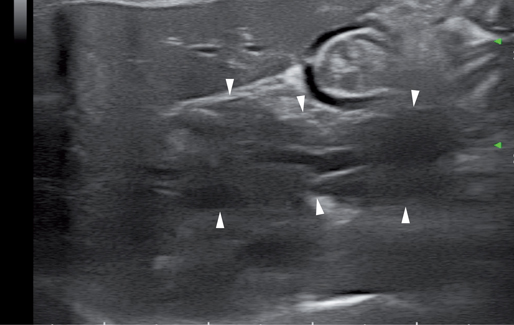

20%的猫会有副胰管直接汇入十二指肠小乳头。胰管位于胰腺实质的中央,宽度为0.5-2.5mm,管壁呈高回声,管腔呈低回声。有研究表明胰管的宽度会随着年龄的增长而增加(图8.表1)。